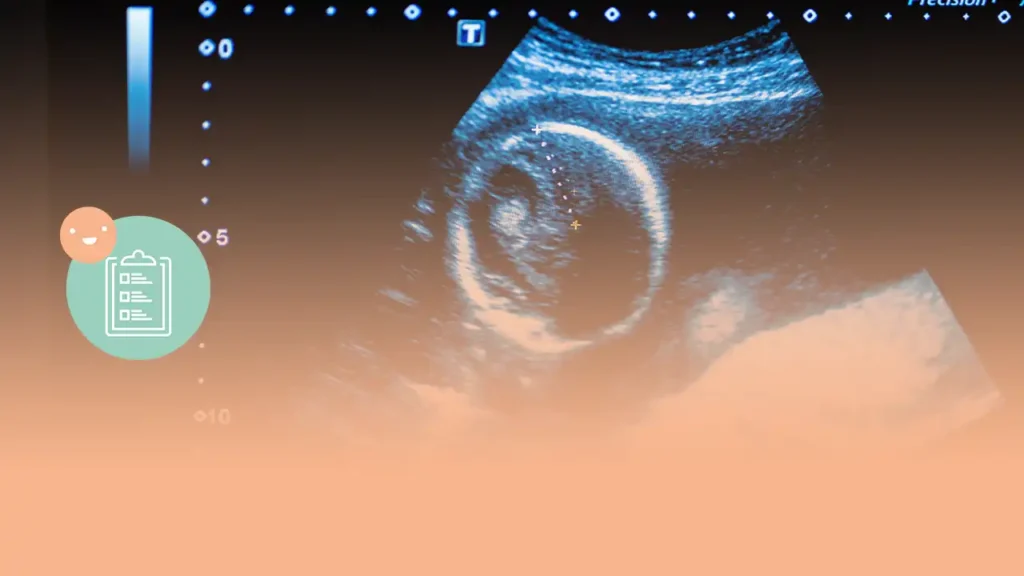

La primera ecografía del embarazo es un momento importante para confirmar la gestación y descartar complicaciones. Se lleva a cabo entre las 11 y 13 semanas de gestación. Durante este examen, se evalúa el desarrollo del feto y se pueden detectar posibles malformaciones. También se realizan mediciones y pruebas adicionales para determinar el riesgo de anomalías cromosómicas. Es fundamental seguir las recomendaciones durante el embarazo, como llevar una alimentación saludable y evitar factores de riesgo. En el siguiente artículo, encontrarás más información sobre la primera ecografía en el embarazo.

La primera ecografía del embarazo es un momento crucial para los futuros padres. Permite confirmar la gestación y descartar la posibilidad de un embarazo ectópico. Además, brinda la oportunidad de verificar el número de sacos y embriones presentes, lo que facilita la detección de embarazos múltiples. Esta ecografía también proporciona valiosa información sobre el desarrollo del feto y la posible presencia de complicaciones.Momento adecuado para realizar la ecografía

Normalmente, la primera ecografía se realiza entre las 11 y 13 semanas de gestación. Este período es ideal porque el feto ya ha desarrollado la mayoría de sus órganos y miembros, lo que facilita una evaluación más precisa. Asimismo, a esta etapa se le conoce como el momento de la “translucencia nucal”, donde se puede medir la cantidad de líquido en la nuca del feto, una indicación importante en la detección de posibles anomalías cromosómicas.Objetivos de la primera ecografía

La primera ecografía tiene varios objetivos clave. En primer lugar, se busca confirmar el embarazo y descartar posibles complicaciones. También se evalúa el desarrollo del feto, se mide su tamaño y se calcula la posible fecha de parto. Además, se realiza una evaluación minuciosa de la anatomía fetal para detectar posibles malformaciones o anomalías. Esta ecografía también puede incluir mediciones y pruebas adicionales para determinar el riesgo de anomalías cromosómicas, lo que ayudará a orientar sobre la necesidad de realizar pruebas de confirmación invasivas.Desarrollo del feto en la etapa de 11 a 13 semanas

La medición del tamaño del feto es otra de las características evaluadas en la primera ecografía. Se utilizan diferentes parámetros, como la longitud cráneo-caudal, para obtener una estimación más precisa de la edad gestacional del feto. Esta información es crucial para calcular la fecha probable del parto y adaptar la atención prenatal de manera adecuada.Anatomía fetal y detección de posibles malformaciones